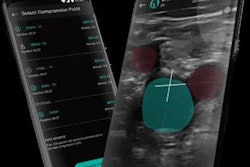

All 93 patients in the study received a systematic ultrasound scan two days after undergoing tracheal intubation. A certified sonographer performed a second ultrasound scan for patients without signs of DVT on the initial scan.